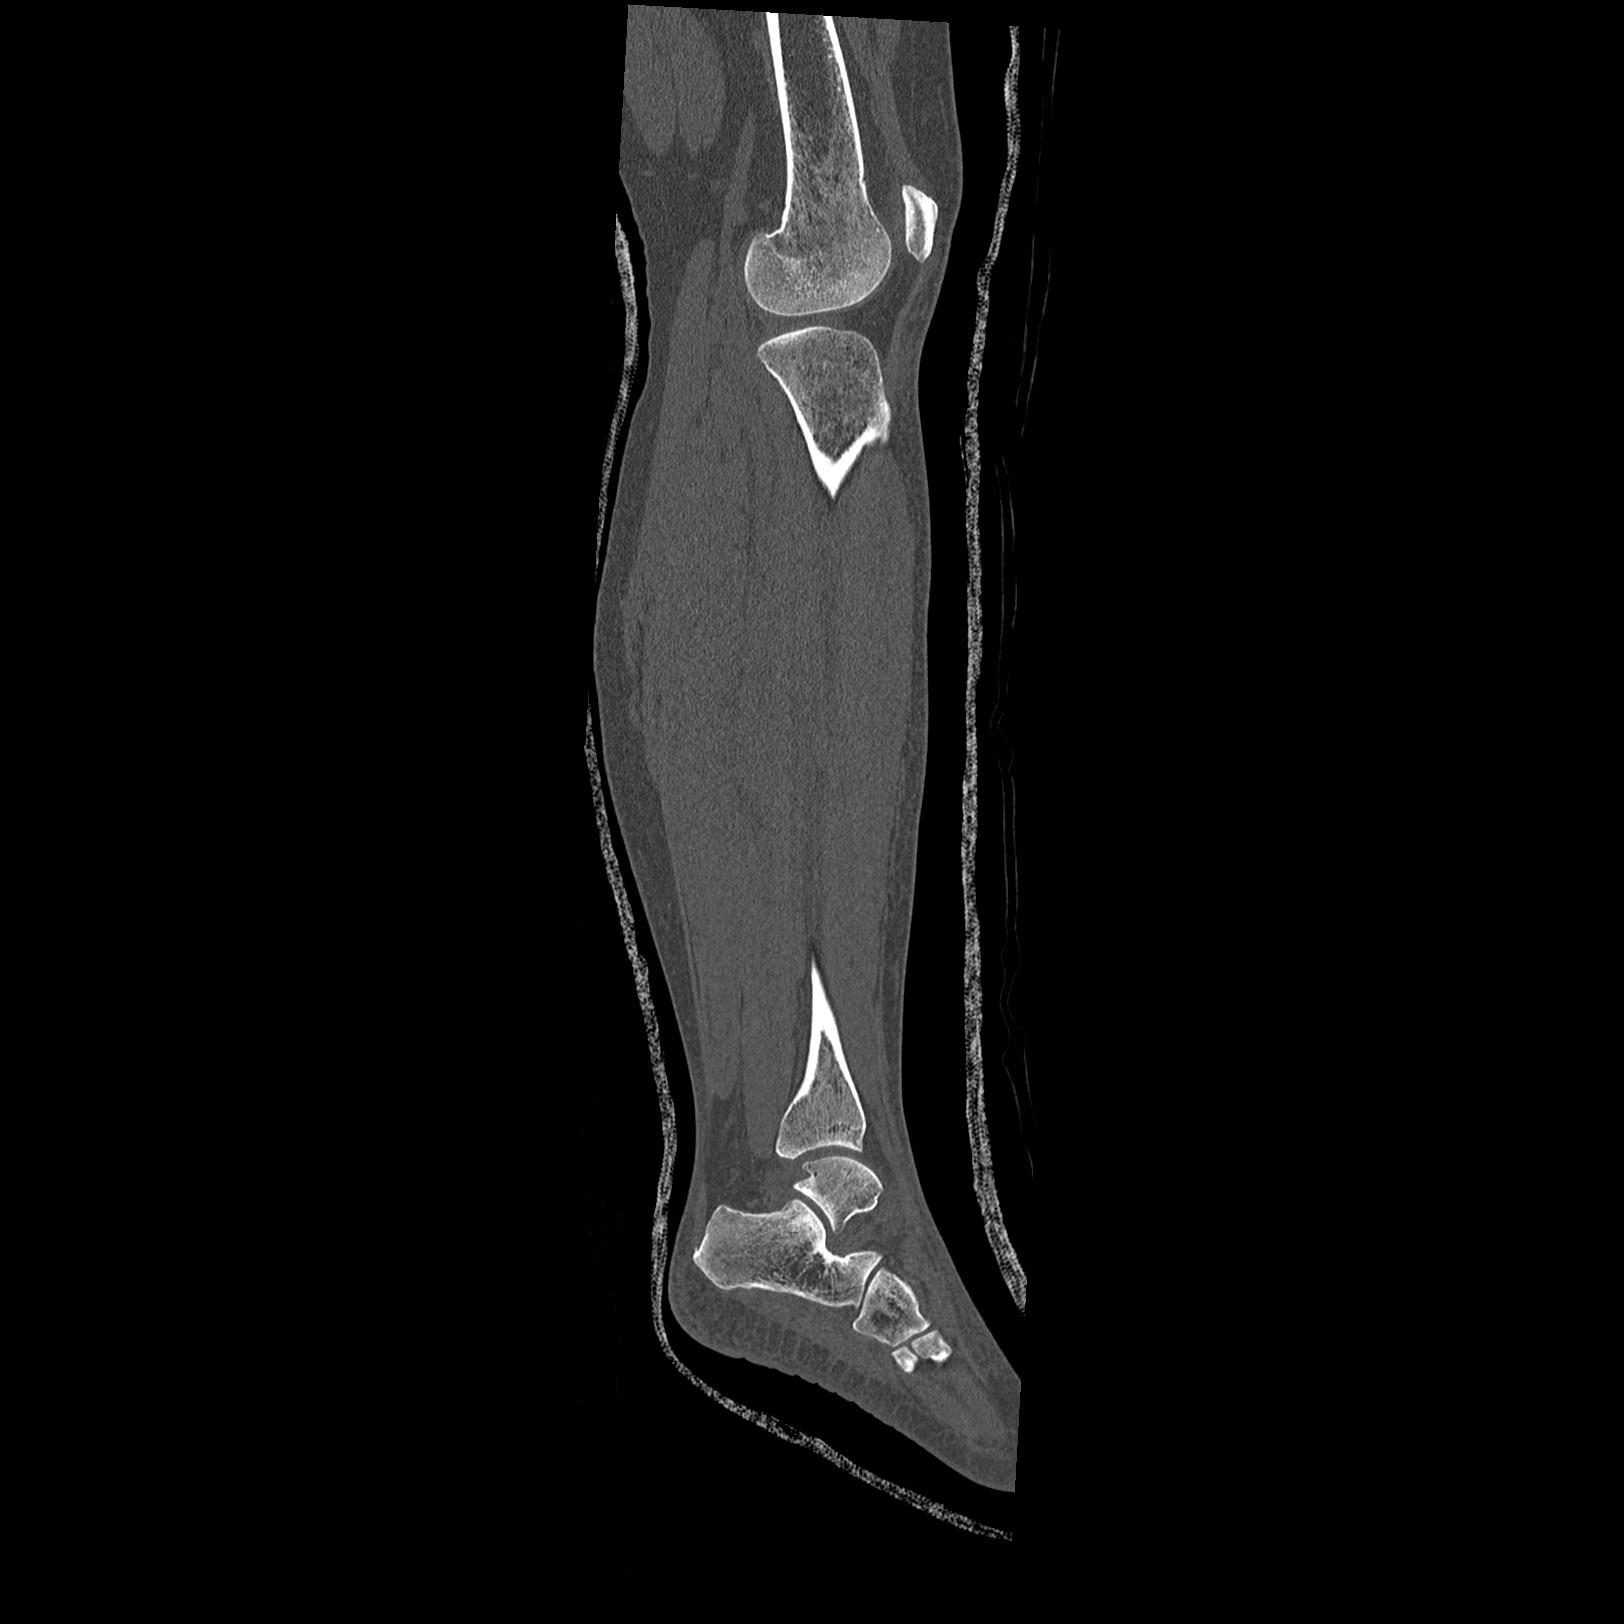

102755 1/4 2R 1/15 2R 右足関節 68歳女性 右三果脱臼骨折